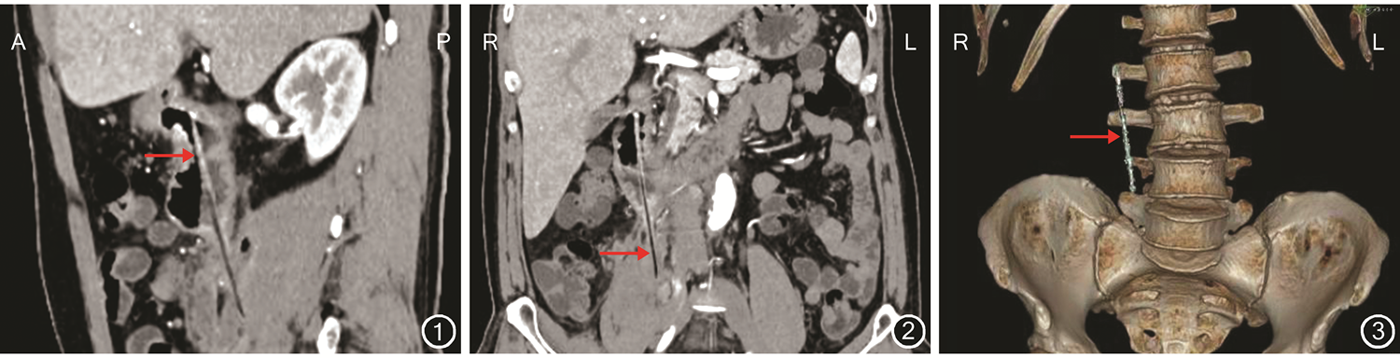

患者男,52岁。因右季肋区及腰背部疼痛10 d伴发热入院。患者10 d前无明显诱因出现右季肋区及右侧腰背部疼痛,伴恶心、呕吐,肛门排气、排便停止。曾于当地医院就诊,腹部X线片检查结果示部分肠道扩张,口服头孢哌酮后病情未好转,遂就诊于我科。患者有原发性高血压病史10年,无心脏病史、糖尿病史;自述6年前曾酒后吞食木筷,无明显症状,未予诊断与治疗。患者入院体格检查:体温38.0 ℃,心率78次/min,呼吸17次/min,血压150/100 mmHg(1 mmHg=0.133 kPa);腹部膨隆,轻度腹胀,右季肋区压痛、反跳痛、局部肌紧张;移动性浊音阴性,肠鸣音减弱;右肾区叩击痛,右输尿管走行区可疑压痛,其余体格检查均为阴性。患者入院辅助检查:WBC计数14.38×109/L,嗜中性粒细胞85%,C-反应蛋白20.44 mg/L。患者术前拒行胃镜检查。腹部增强CT检查结果显示:十二指肠降部条状高密度异物影,边界清晰,异物穿破十二指肠降部向下刺入右侧腰大肌,腹膜后少量积气伴周围脓肿形成,病灶局部与右侧输尿管中段分界不清晰。见图1, 2, 3。